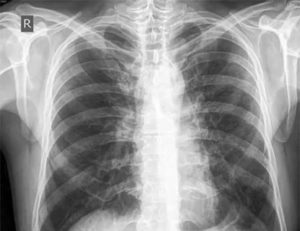

Изменения в легких, как правило, обнаруживаются врачом-рентгенологом в ходе плановой диспансеризации. О метатуберкулезных (meta – после перенесенного) изменениях говорят, как о рентгенологическом термине, хотя на самом деле изменения могут быть опасными для жизни.

Метатуберкулезом называют очаги разрастания соединительной ткани или отложения кальция в том месте, где предположительно до этого был туберкулез. Увидеть их можно с помощью обзорной рентгенограммы.

И чаще всего эта проблема никак не проявляет себя клинически, а определяется только при проведении рентгена или флюорографии. Лечения обычно не требует. Но наблюдение врача-фтизиатра – необходимо.

Посттуберкулезные изменения хорошо видны на рентгенограмме в виде уплотнений, затемнений или уменьшения объема легкого, изменения сосудистого рисунка. Для изучения функции легких проводится спирометрия, во время которой исследуется: